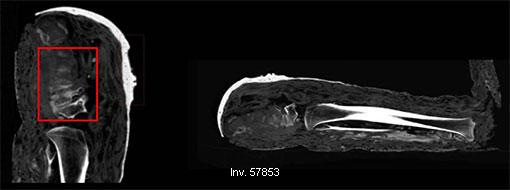

2015.01.21.

A Vatikáni Múzeum egyiptomi gyűjteményében őrzött két múmiáról szakemberek megállapították, hogy későbbi évszázadokban hamisították őket. tovább